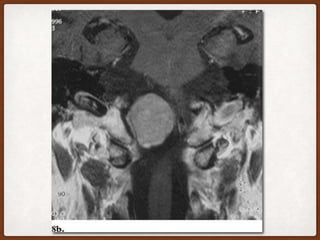

DERMOID CYST • Resultfrom inclusion of ectodermal elements during neural tube closure. • Midline lesions that rarely invade the CPA laterally and contain elements from all layers of the skin. Thus, fat, hair, sebaceous glands, and sweat glands can be found in addition to squamous epithelium. • Typically, dermoid cysts have negative attenuation values on CT scans and high signal intensity on T1-weighted images due to their fatty content, may have a very suggestive fat-fluid level, and contain calcifications .

• 14.